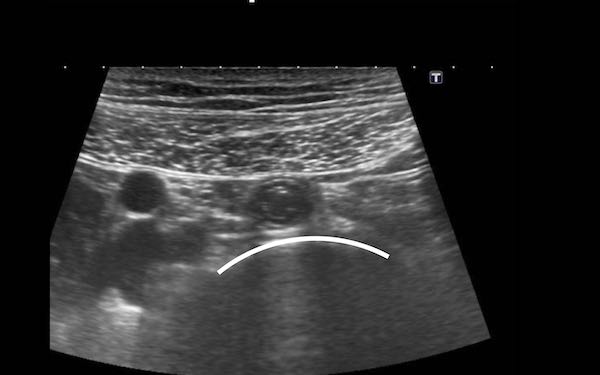

Tá tràng đoạn xuống và đoạn nằm ngang hiếm khi có thể tiếp cận được bằng siêu âm.

Khi được tìm kiếm cụ thể, có thể xác định được các túi thừa tá tràng chứa đầy khí kích thước lớn, hiện diện ở 10-15% dân số bình thường.

Chúng biểu hiện dưới dạng một phản xạ (đường cong) tuyến tính trong đầu tụy.

Lưu ý rằng những bệnh nhân này thường có ống mật chủ rộng hơn so với bệnh nhân bình thường.